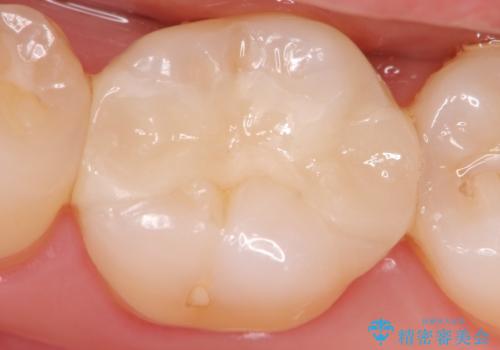

マイクロスコープを用いることで歯の微細な硬さや虫歯の広がりをすみずみまで精査することができます。

しっかりと虫歯を取り除き、精密なインレーを装着することで虫歯の再発を防ぎ長期的な予後を期待できる環境を整えます。